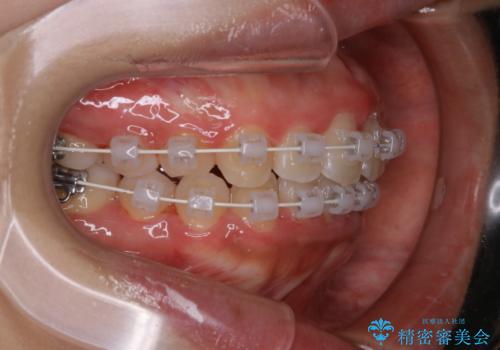

- 矯正装置

- ワイヤー審美装置

- 4年ほど前から地元の歯科医院にてインビザライン治療を行っていたが、引っ越し後に通いづらくなってしまったため、治療が途中で止まってしまっているとの事で来院されました。性格的にインビザラインの継続した使用が難しいとのことで、ワイヤー装置にて最終仕上げを行いました。

インビザラインは20時間以上の装着を厳守して頂くことで治療効果が期待できる治療となります。固定式のワイヤー装置に切り替えることで短期間で歯並びを整えることができ、大変喜んでいただけました。